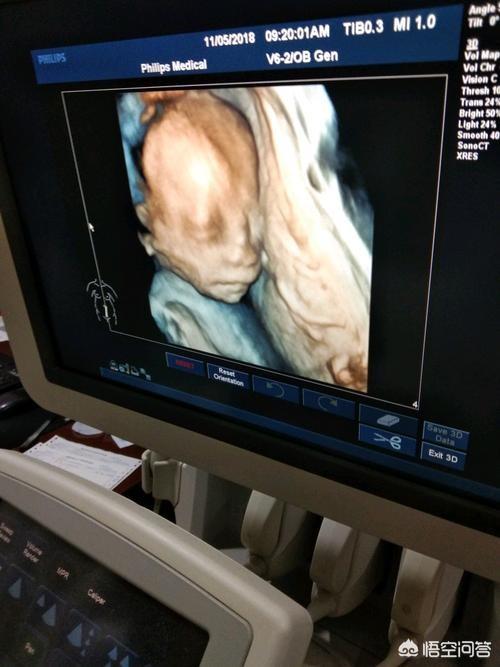

第三次:21-24周

检查项目:四维大排畸

大排畸是孕中期6个月左右对胎儿全身进行检查的项目。而在此之后到胎儿出生通常还需要做至少2次B超。这是很重要的。

大排畸以后。为什么还要再做至少2次B超

检测胎儿发育情况:大排畸以后。还要做至少两次B超是很有必要的。这是因为从怀孕6个月到胎儿出生。还有大概3个多月的时间。如此长的时间。如果不用B超检测。就无法了解胎儿的发育情况。这其中的风险是很大的。